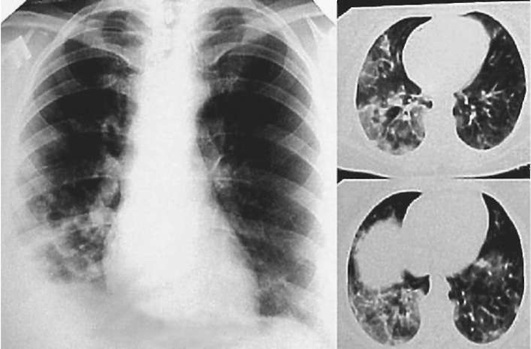

Лучевые методы исследования. Рентгенологическая картина при ЭТА зависит от стадии заболевания. В начальной фазе выявляются признаки отека интерстициальной ткани легких и распространенные мелкоочаговые затенения. При прогрессировании процесса формируются двусторонние изменения легочного рисунка по типу интерстициального фиброза, преимущественно в нижних отделах легких (рис. 2.28). В далеко зашедших случаях определяется мелко- и крупноячеистая деформация легочного рисунка. Описаны случаи, когда единственным рентгенологическим признаком болезни был односторонний плевральный выпот. Отсутствие каких-либо изменений на рентгенограммах отнюдь не исключает ЭТА. Так, при бериллиозе у 23-59% больных может выявляться умеренно выраженная двусторонняя лимфоаденопатия, а в ряде случаев - рентгенотрицательная форма бериллиоза (Dweik R.A., 2015). У 30% из 71 больных ЭТА, наблюдавшихся нами в клинике пульмонологии, в момент обследования изменений на рентгенограммах не было (Орлова Г.П., 2019). Группа больных ЭТА была обозначена условно как рентгенотрицательная группа. Уточнить диагноз помогает КТ легких, выявляющая интерстициальные изменения в легочной ткани по типу «матового стекла», усиление и деформацию легочного и сосудистого рисунка (рис. 2.29), фиброзные изменения тяжистого и звездчатого типов, на поздних стадиях - «сотовое легкое». ВРКТ выявляет «матовое стекло» и другие изменения в легочной паренхиме, которые не видны при обычном рентгенологическом исследовании. Но даже ВРКТ не всегда выявляет изменения в легочной ткани. Так, в 25% случаев гистологически подтвержденного хронического берил-лиоза легких ВРКТ была нормальной (Dweik R.A., 2013; Амосов В.И., Сперанская А.А., 2015; Amanullah S. et al., 2015).

Рентгенологические изменения в легких при ингаляционных лихорадках также могут отсутствовать или проявляться в виде летучих инфильтратов (Ahsan S.A. et al., 2009; Shimizu T. et al., 2012; Greenberg M.I. et al., 2015). При бериллиозе, помимо диффузных инфильтратов и усиления легочного рисунка, за счет интерстициального компонента у 23-59% больных может выявляться лимфаденопатия (Sirajuddin A. et al., 2009).

Проведенное нами динамическое исследование КТ-паттернов у 42 больных ЭТА показало трансформацию отдельных типов интерстициальных пневмоний по мере прогрессирования патологического процесса в фиброзную НСИП или ОИП (рис. 2.30), что подтверждает объединительную концепцию интерстициальных пневмоний вне зависимости от этиологического фактора, которые являются не отдельными нозологическими формами, а стадиями течения фиброзирующего процесса в легких (Илькович М.М., Новикова Л.Н., 2018; Орлова Г.П. и др., 2019).